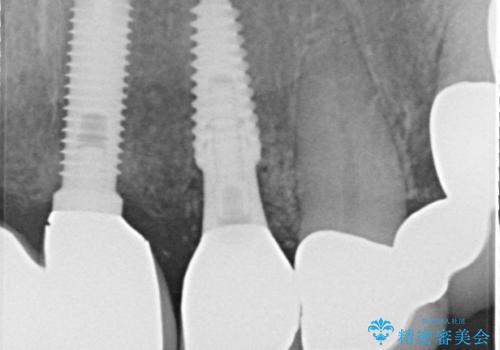

初回カウンセリング時にはセラミッククラウンが装着されていましたが、インプラント治療でのご来院時には前歯は外れて紛失をしてしまったとのことでした。

事前に仮歯の型取りをして用意をしていたため、インプラント埋入後に速やかに仮歯を装着しました。

インプラントの安定度も高く、抜歯と埋入から2か月後にはオールセラミッククラウンを装着することができました。